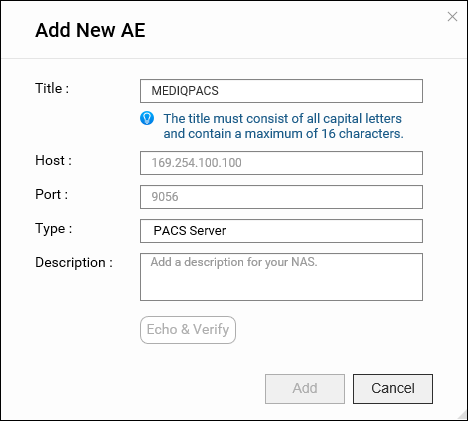

应用实体 (AE) 管理

在 DICOM 中,应用实体 (AE) 表示 DICOM 网络中的端点系统或程序,例如设备或 PACS 服务器。将 NAS 配置为 PACS 服务器时,将它视为一种 AE。

在 MediQPACS 的“AE Management”(AE 管理)屏幕中,用户可以在本地或外部网络上添加、编辑、删除、搜索和测试其他 AE 的连接。

添加新 AE